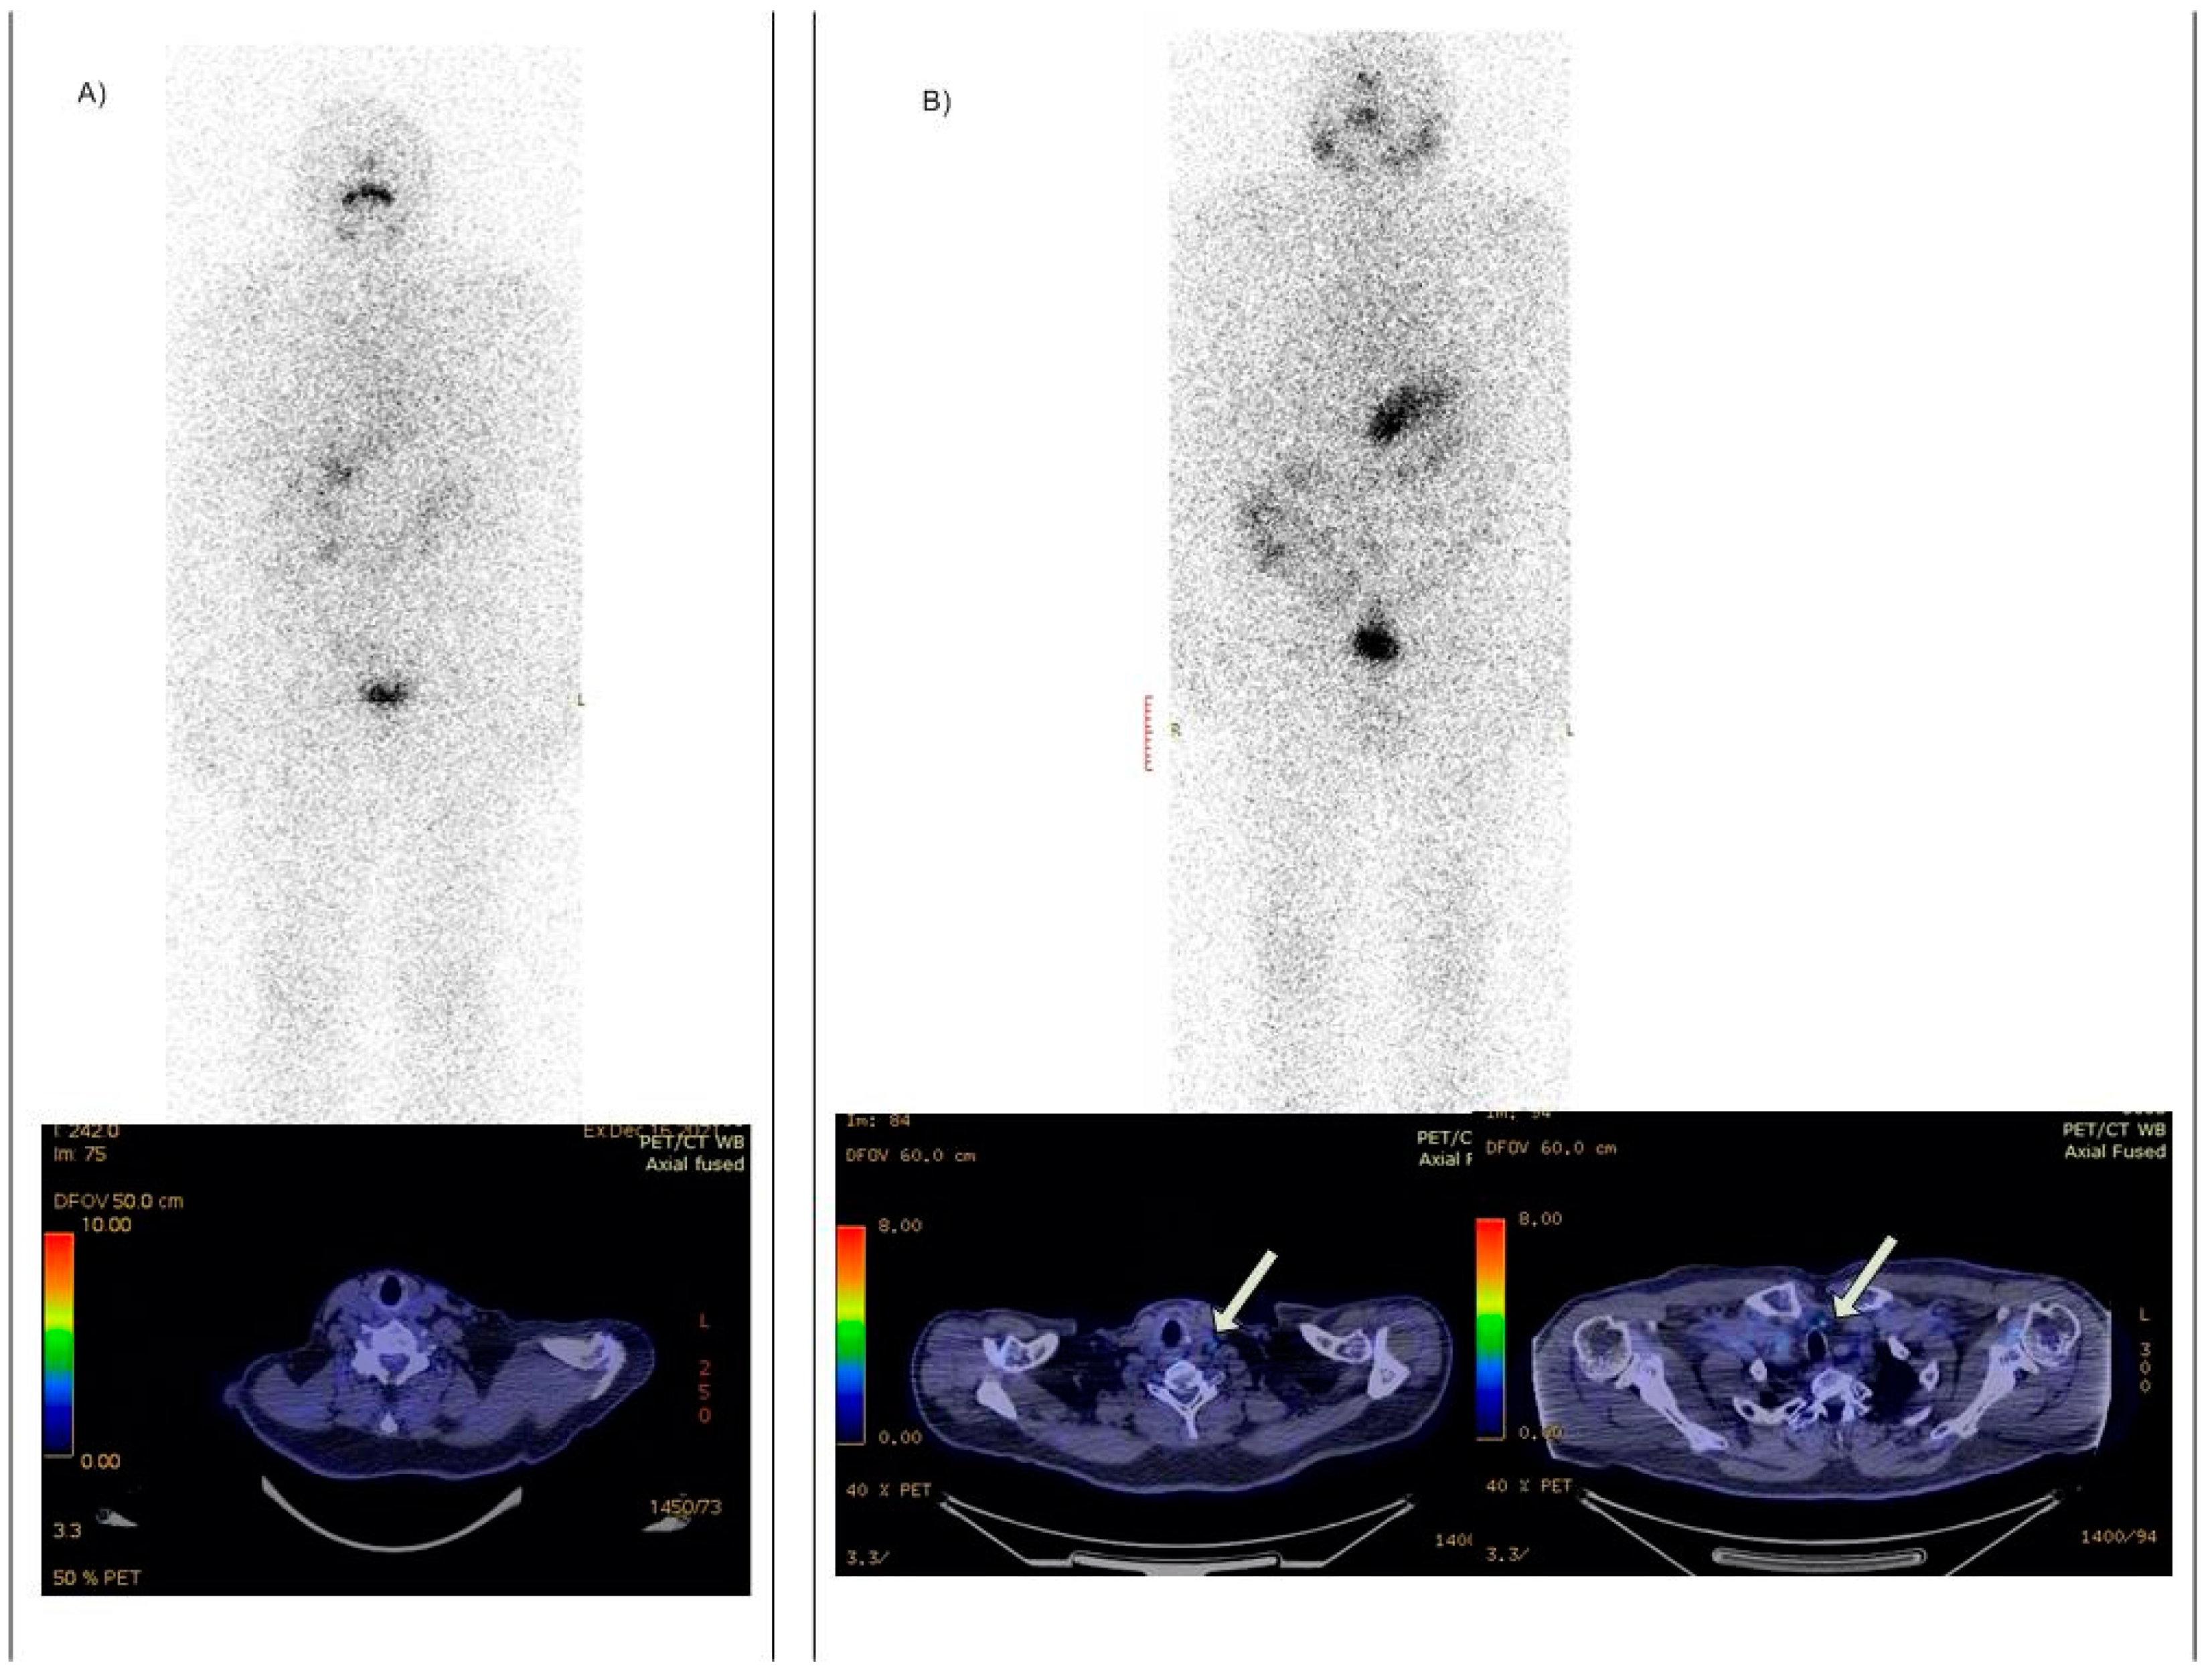

- Versari, A.; Sollini, M.; Frasoldati, A.; Fraternali, A.; Filice, A.; Froio, A.; Asti, M.; Fioroni, F.; Cremonini, N.; Putzer, D.; et al. Differentiated thyroid cancer: A new perspective with radiolabeled somatostatin analogues for imaging and treatment of patients. Thyroid 2014, 24, 715–726. [Google Scholar] [CrossRef] [PubMed]

- Roll, W.; Riemann, B.; Schäfers, M.; Stegger, L.; Vrachimis, A. 177Lu-DOTATATE therapy in radioiodine-refractory differentiated thyroid cancer: A single center experience. Clin. Nucl. Med. 2018, 43, e346–e351. [Google Scholar] [CrossRef]

- De Vries, L.H.; Lodewijk, L.; Braat, A.J.A.T.; Krijger, G.C.; Valk, G.D.; Lam, M.G.E.H.; Rinkes, I.H.M.B.; Vriens, M.R.; De Keizer, B. 68Ga-PSMA PET/CT in radioactive iodine-refractory differentiated thyroid cancer and first treatment results with 177Lu-PSMA-617. EJNMMI Res. 2020, 10, 1–8. [Google Scholar] [CrossRef]